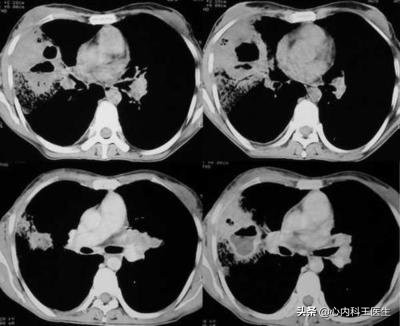

肺脓肿患者肺部CT有何特点?

患者肺部CT表现为浓密片状阴影有液平或空洞形成,病变发生在右肺多于左肺。